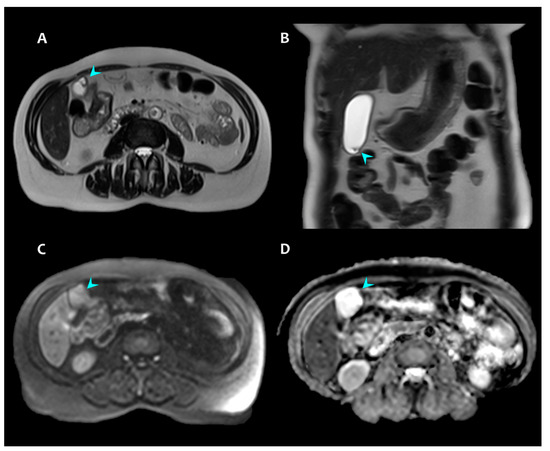

2. Presentation of Case #1

3. Presentation of Case #2